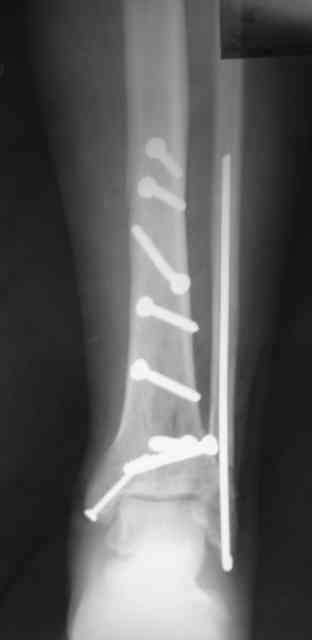

Сегодня прооперировали. Длительность 4-50. Начали как и говорил сверху вниз линейным разрезом - фиксация задне-латерального отломка к проксимальному 2мя винтами, затем "прилепили" к ним передне-медиальный (пришлось повозиться - была интерпозиция и довольно "сложный" винт) - к проксимальному 1 винтом и к задне-латеральному 1 винтом.Кстати на фото видно - у передне-медиального отломка еще осколок в области сустава, несколько смят. Далее началось веселье - второй доступ - задне-наружный к латеральной лодыжке и заднему краю, но оказалось, что задний край больше задне-медиальный (по снимкам было непонятно). Плюс к этому репозиция его мягко говоря сложновата (больной на спине, стол низкий и не поднимается). В общем выставили, фискировали 2мя винтами, на ЭОПе вроде стал, только верх отошел. Латеральную лодыжку заведующий решил интрамедуллярно (не хотел еще винты толкать), сначала 3мм спицей - нестабильно, затем 4мм стержень (не помню по автору) - ОК (кстати в месте перелома мелкая крошка - дефект до 5х7 мм по кортикалу). Ну медиальная лодыжка стандартно - третий разрез - винт 3,5 мм. Визуально все стабильно. На Р-контроле - видна небольшая ступенька заднего края по одному из контуров.

Рентгенограммы

На фото простой суставной, метафиз. оскольчатый с переходом на диафиз перелом, пластина MIPO.